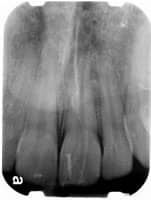

Periapical X-ray

highlight only one or two teeth at a time. A periapical X-ray looks similar to a bite-wing X-ray. However, it shows the entire length of each tooth, from crown to root.